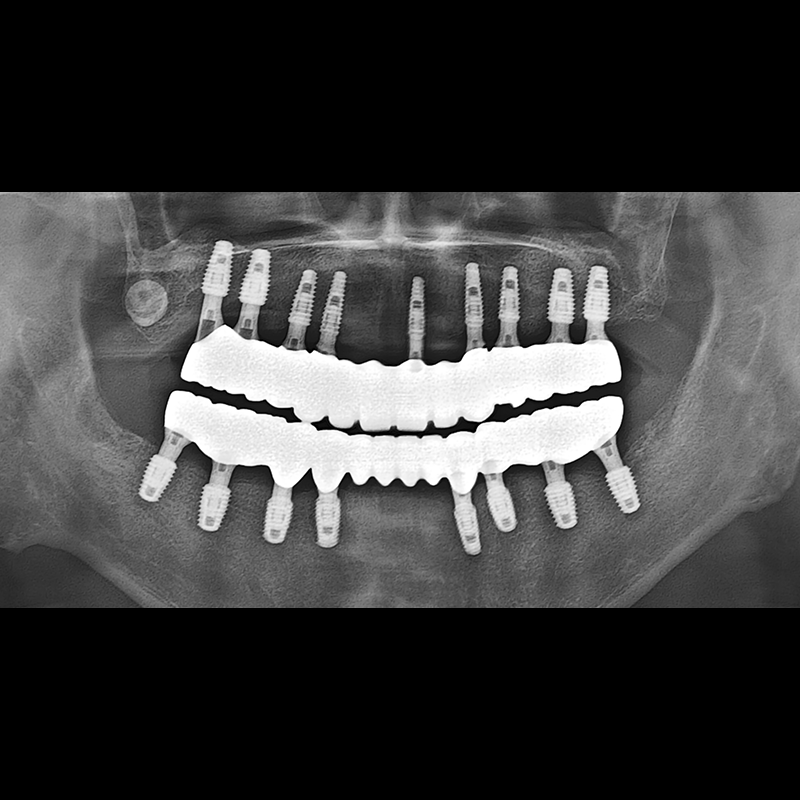

BEFORE AFTER

种植牙前后的照片 2025.05.30

在缺失的牙齿部分和难以挽救的牙齿位置植入了种植牙。